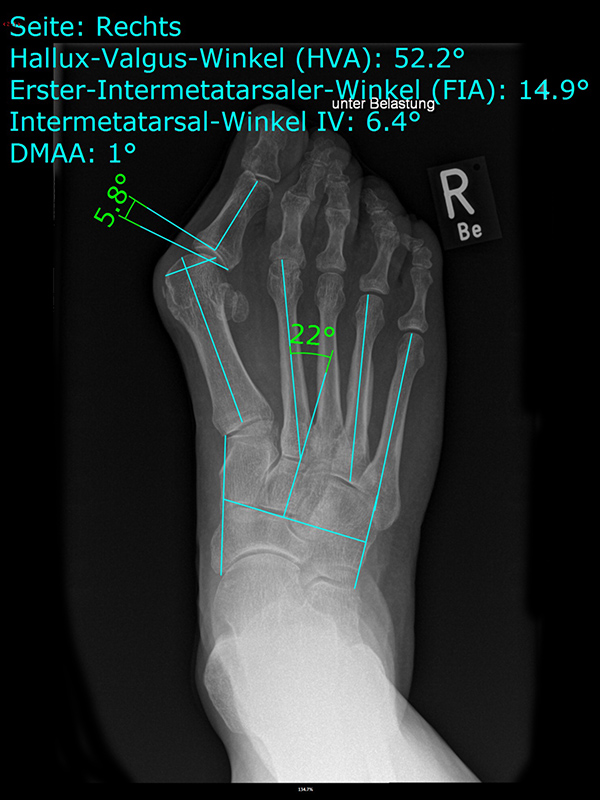

• Folgende Winkel können präoperativ zur Erleichterung der Planung am Röntgenbild eingezeichnet werden:

• IMW (Intermetatarsalwinkel).

• HVW (Hallux valgus-Winkel).

• DMAA (Distal Metatarsal Articular Angle) – Planung der ggf. notwendigen Reverdin-Isham-Osteotomie.

• PPAA (Proximal Phalangeal Articular Angle) – Planung der ggf. notwendigen Akin-Osteotomie.

• VAW (Vorfußadduktionswinkel) – Planung der Ausrichtung der DMMO (Distalen minimalinvasiven Metatarsale Osteotomien).

Einschränkend ist anzumerken, dass o.g. Winkel projektions- und rotationsabhängig sind 15. Daher ist intraoperativ die Planung anhand von Bildverstärkeraufnahmen zu verifizieren und ggf. anzupassen.